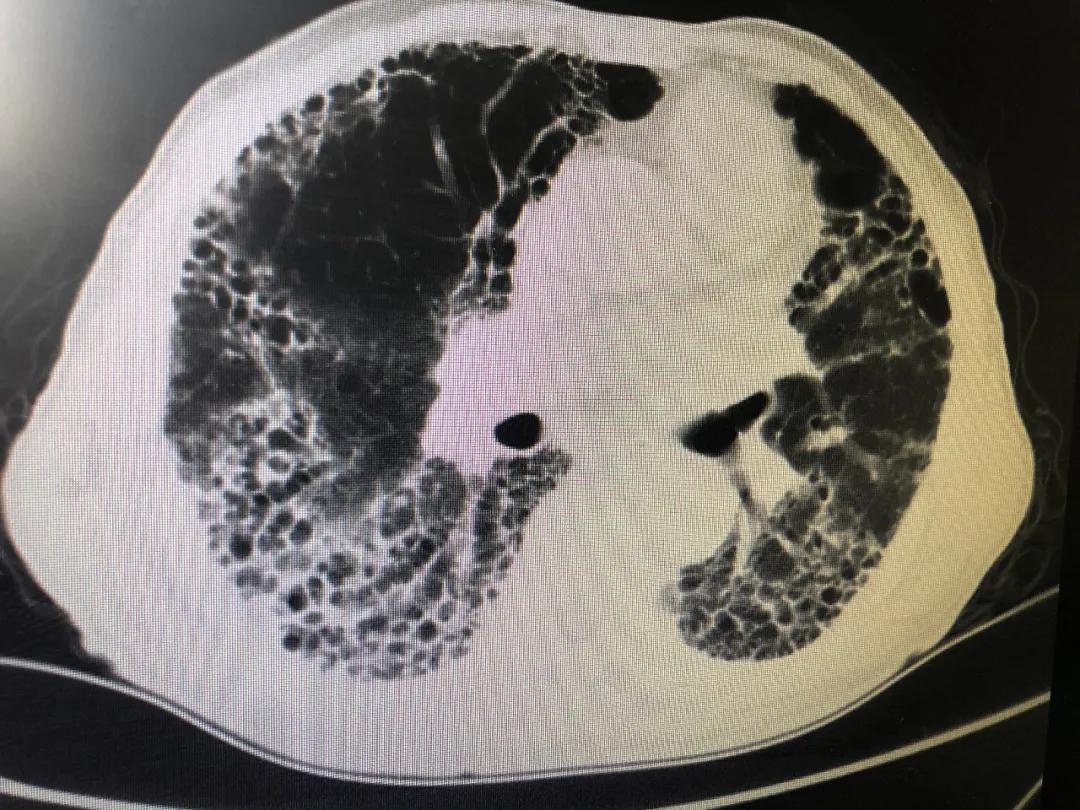

刘大爷近2年病情逐渐加重,几乎每1-2个月都需要住院治疗。今年6月下旬再次因气短加重伴发热到三院呼吸科治疗,此次病情比以往更加严重,持续高热、剧烈的咳嗽、严重呼吸困难;出现呼吸衰竭、心力衰竭、肝功能不全、低蛋白血症等多器官功能衰竭,且合并冠心病、类风湿性关节炎等多种基础疾病,病情极其危重。

刘大爷入院后,侯凤茹主任高度重视,带领整个呼吸科医疗团队立即投入紧张的抢救治疗中,通过准确地判断病情,明确诊断为特发性肺间质纤维化急性加重合并严重的肺部感染。侯主任积极组织科内研究讨论病情,充分认识到该患的肺感染存在耐药的铜绿假单胞菌和真菌的多重感染,同时存在因严重的缺氧导致的多脏器衰竭。刘大爷病情重危,命悬一线﹍﹍。